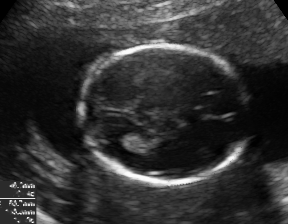

We demonstrate the practical applicability of our method on a challenging medical application, the classification of standardized fetal ultrasound (US) views during prenatal screening. In many countries, US imaging is clinical routine for prenatal health care. The classification of standardized views is important for a consistent, cross-institutional identification of possible abnormalities [47]. Early detection of pathological development can inform following treatment and delivery options [55, 25]. DNNs have shown promising performance to support this task [2]. However, ultrasound images are often hard to interpreted [40]. Anatomical structures have inconsistent appearance [2] and contain different orientations and shapes of anatomical landmarks [1]. Labeled training data is often insufficient as annotating medical images requires significant expertise and is prohibitively expensive in both time and labor. Manifestation of acoustic shadows [17, 44] as shown in Fig. 2(a) as well as different imaging devices as shown in Fig. 2(b) can lead to a domain shift problem for vanilla DNN classifiers. Exploring domain adaptation in fetal US enables DNN classifiers to be effectively utilized on a wider range, which supports identification of abnormalities from varying data sources. This can benefit prenatal healthcare.

We evaluate the proposed method on two fetal US standard plane classification tasks, where the domain shifts are respectively caused by shadow artifacts (Fig. 2(a)) and different image acquisition devices (Fig. 2(b)). For both tasks, images from source and target domains are unpaired and collected independently. We show the key results in the main paper and detailed implementation, network architectures as well as more results in the supplemental Appendix.

The fetal US dataset consists of 2D fetal US images sampled from 2694 2D US examinations with gestational ages between weeks (iFIND Project 555http://www.ifindproject.com/ ). Eight different US systems of identical make and model (GE Voluson E8) were used for the acquisitions to eliminate as many unknown image acquisition parameters as possible. Six different anatomical standard plane locations have been selected by an experienced sonographer, including Four Chamber View (4CH), Abdominal, Femur, Lips, Left Ventricular Outflow Tract (LVOT) and Right Ventricular Outflow Tract (RVOT). The images have additionally been classified by an expert observer as shadow-containing or shadow-free. In this experiment, the source domain contains shadow-free images (see Fig. 2 (b) SF) while the target domain has shadow-containing images from less favorable imaging conditions (see Fig. 2 (b) SC). Training data consists of all six standard planes from the source domain as well as Abdominal, LVOT and RVOT from the target domain. We aim to separate anatomical features (categorical features) and shadow artifacts features (domain features) to obtain generalized anatomical features for achieving high performance of standard plane classification on (4CH, Femur and Lips from target domain). Here, contains 4CH, Abdominal, Femur, Lips, LVOT and RVOT from the source domain and contains Abdominal, LVOT and RVOT from the target domain. Hyper-parameters to in Eq. 11 are for the proposed MIDNet model and is additionally for MIDNet+.